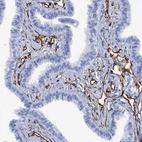

Immunohistochemistry analysis in human lung and skin tissues using HPA039325 antibody. Corresponding SDPR RNA-seq data are presented for the same tissues.